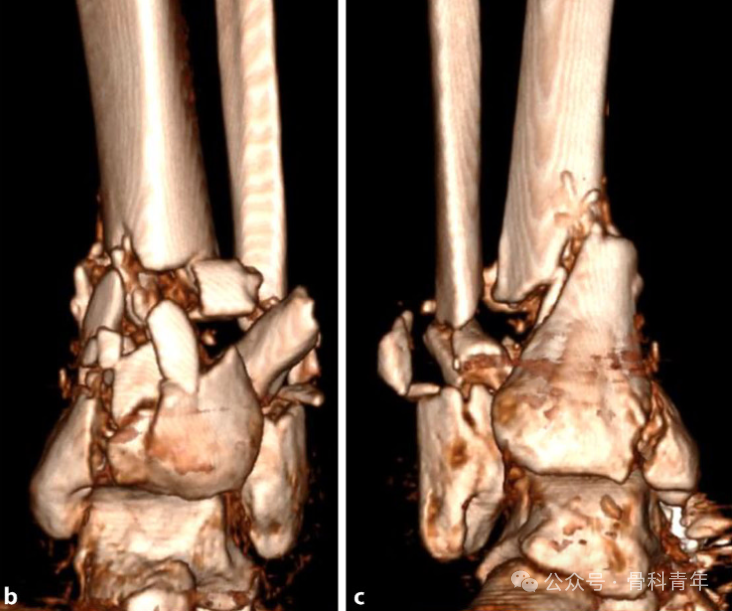

扫描(Scan):进行 CT 检查,包括三维重建;